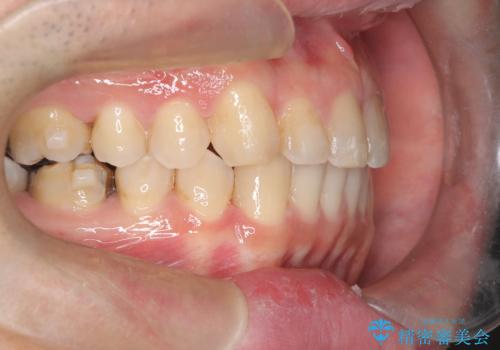

正中離開・クロスバイト・すきっ歯・叢生|インビザラインで治療

- 前歯の隙間と歯のデコボコを主訴にご来院された患者様です。

加えて、上下の奥歯が全く咬み合わないシザーズバイトの状態も認められました。

矯正検査の結果、非抜歯でインビザラインによる治療が可能と判断し、治療を行いました。

歯の隙間とデコボコ、シザーズバイトも改善され、咬み合わせや見た目が整い、患者様にも大変ご満足いただけました。